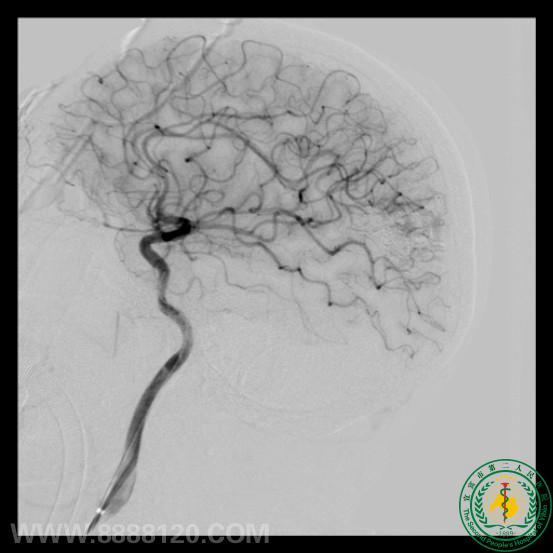

我科成功完成1例复杂动静脉畸形介入治疗

我科成功完成1例复杂动静脉畸形介入治疗9058